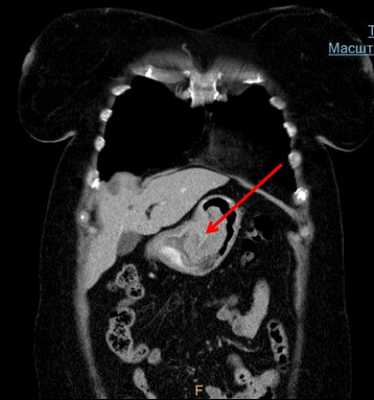

По данным ЭГДС, выполненной при поступлении: на фоне недостаточности кардии и неэрозивного рефлюкс-эзофагита на уровне 33 см от резцов по заднеправой стенке пищевода расположено экзофитное новообразование полиповидной формы размером 8×5 мм белесой окраски, выступающее в просвет на 4—5 мм, симптом шатра отрицательный (рис. 1, 2). Поверхность новообразования гладкая, сосудистый рисунок прослеживается.

Пациенту выполнена эндоскопическая ультрасонография (ЭУС): при сканировании мини-зондом UM-G 20-29 R частотой 20 MHz определяется гипоэхогенное образование овальной формы с четкими контурами, однородной консистенции, расположенное в толще слизистой оболочки и подслизистого слоя пищевода, при этом оно интимно прилежит к мышечной стенке, что не позволяет исключить инвазию образования в мышечный слой. Заключение ЭУС: неэпителиальное новообразование пищевода, исходящее из глубокого слоя слизистой оболочки и подслизистого слоя. При компьютерной томографии органов грудной клетки патологии не выявлено. По данным выполненной ранее щипцовой биопсии и гистологического исследования определена морфологическая принадлежность образования — шваннома.

Образование извлечено с помощью эндоскопической петли и направлено на гистологическое исследование. На месте удаленного образования определялся дефект слизистой оболочки до 2 см в диаметре без визуальных признаков повреждения мышечного слоя стенки пищевода (рис. 5). В послеоперационном периоде пациенту рекомендована щадящая диета с исключением грубой пищи, проведена антисекреторная терапия ингибиторами протонного насоса. В 1-е сутки после операции ESD выполнено рентгенологическое контрастное исследование с целью исключения перфорации стенки пищевода с учетом первого опыта диссекции. Затекания контрастного вещества за контуры пищевода не отмечалось (рис. 6, 7).

Рис. 6. Контрастная рентгенограмма пищевода. Затекания контрастного вещества за контуры пищевода нет.

Рис. 7. Контрастная рентгенограмма пищевода. Затекания контрастного вещества за контуры пищевода нет.